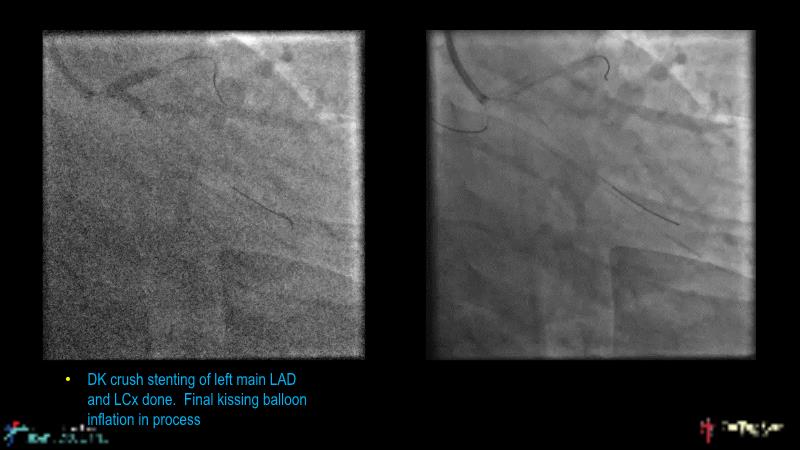

This session is recommended for you if you are seeking insights into the advantages of using IVUS imaging over visual assessment for better outcomes in left main bifurcation procedures. Discuss with experts the benefits of using RotaCUT in lesion preparation for left main bifurcation and explore the impact of high radial strength stents on the procedure's success.

• To understand why the use of IVUS imaging is different from seeing with experienced eyes to achieve improved left main bifurcation outcome

• To see advantages of RotaCUT as part of lesion preparation in left main bifurcation

• To know how a high radial strength stent can make a difference in left main bifurcation